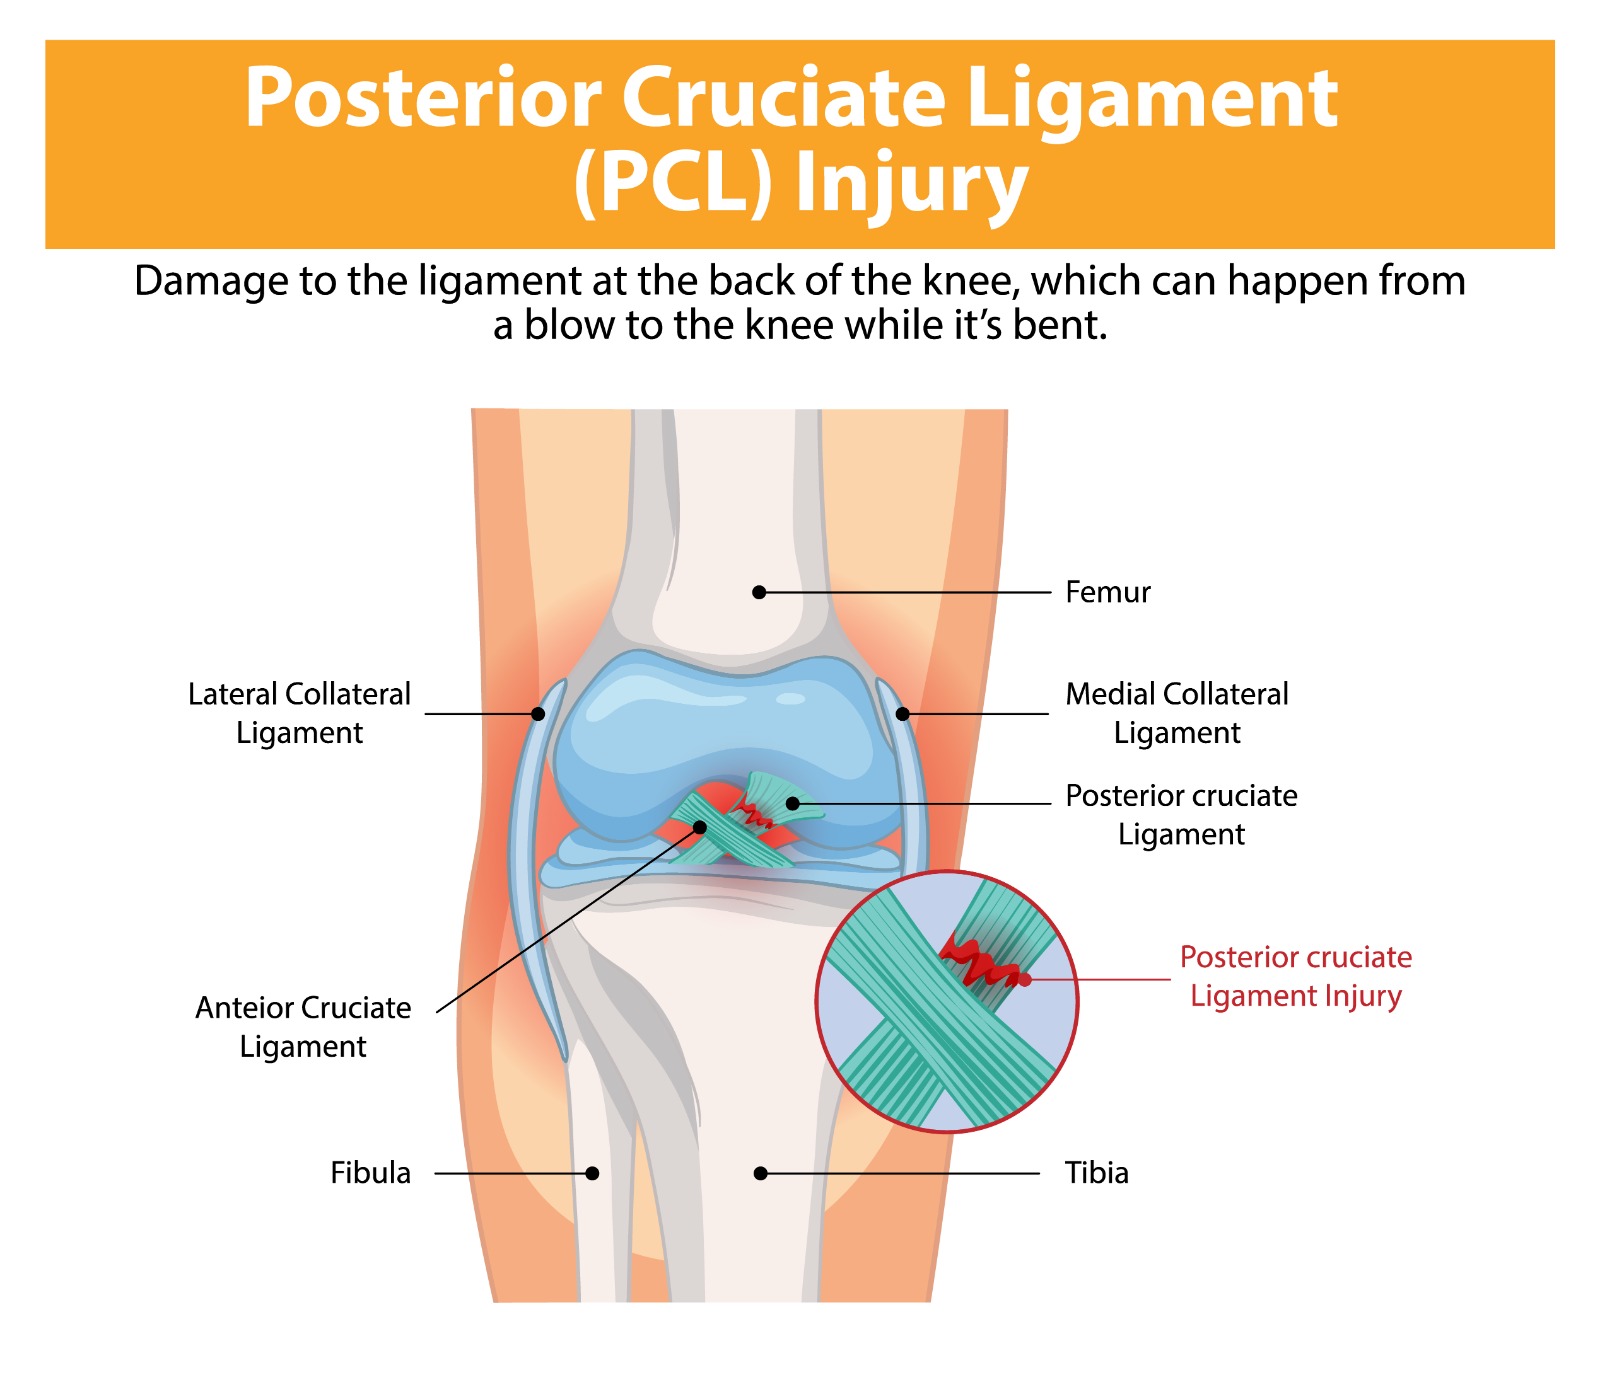

The posterior cruciate ligament (PCL) is the strongest ligament in the knee, preventing the tibia from sliding backwards relative to the femur. PCL injuries, though less common than ACL tears, account for a significant proportion of serious knee ligament injuries — particularly in contact sports, road traffic accidents, and high-energy trauma. They range from isolated grade I sprains to complete grade III ruptures, often occurring alongside injuries to other knee ligaments in complex multi-ligament knee injuries.

The posterior drawer test and posterior sag sign are the key clinical tests. Stress X-rays quantify the degree of posterior tibial translation. MRI confirms PCL injury and identifies associated ligament, meniscal, and chondral pathology. CT angiography may be required if knee dislocation is suspected.